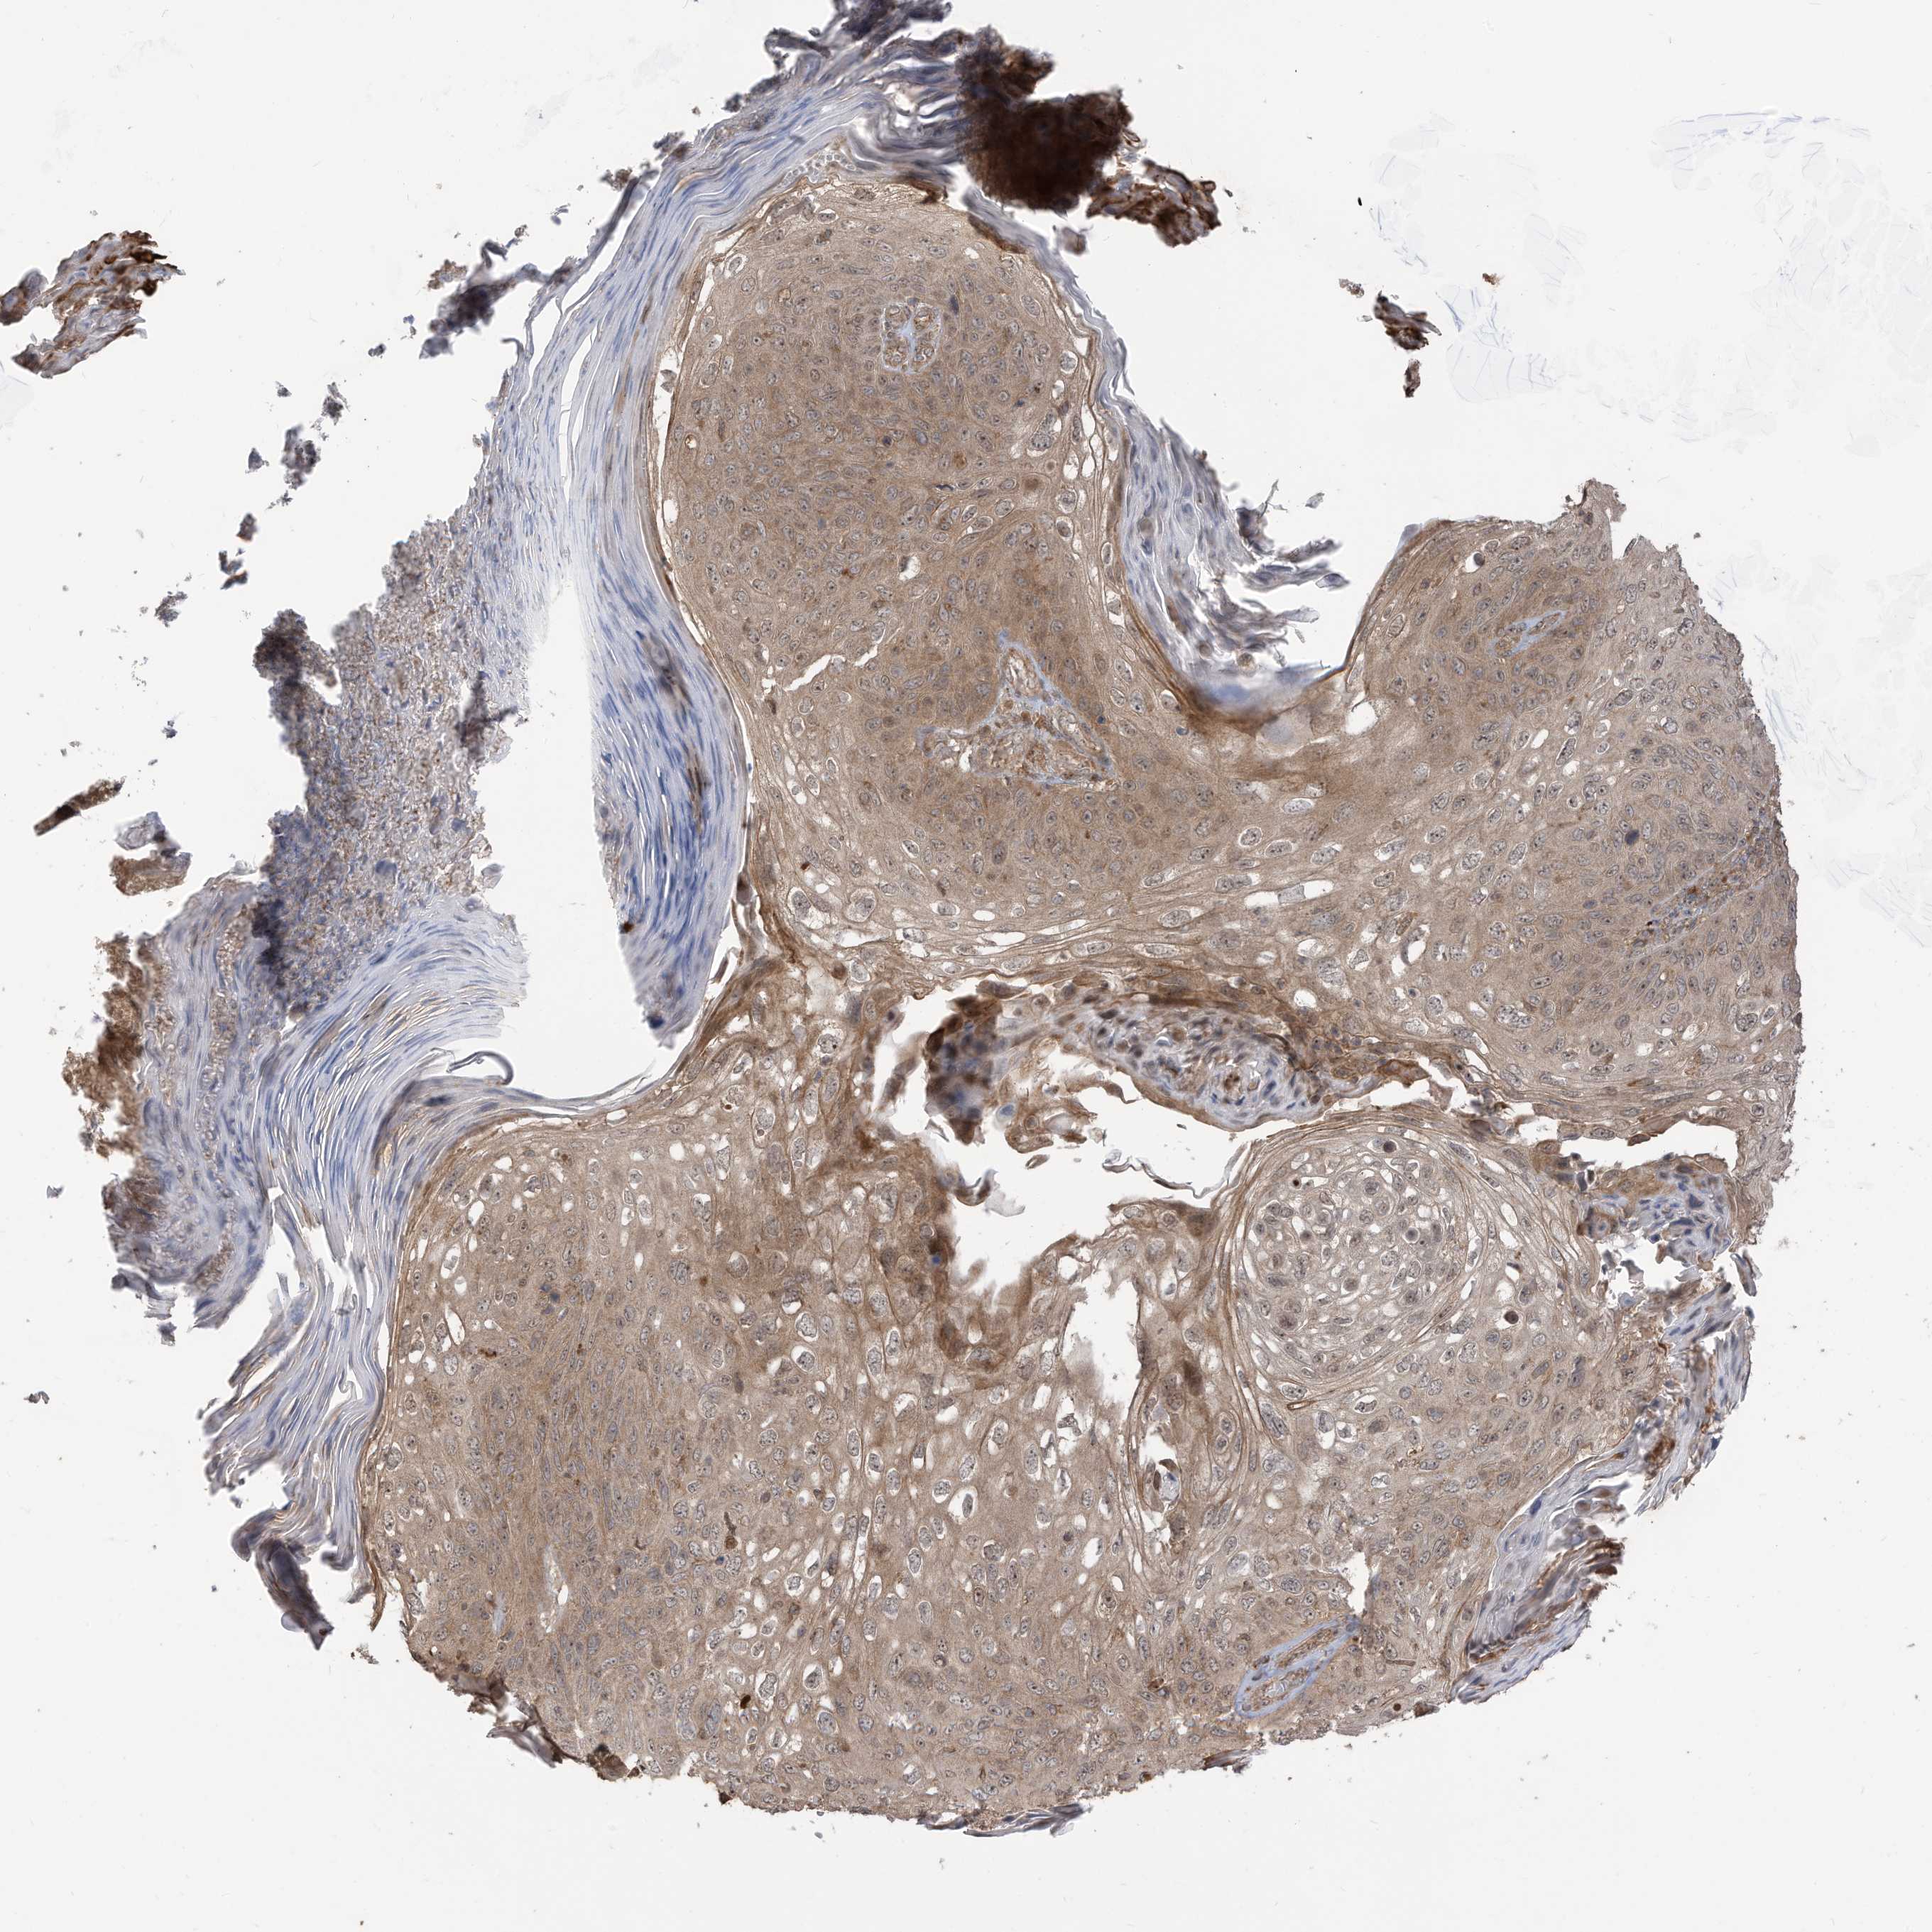

SKIN CANCER - Protein expressioni

A mouse-over function shows sample information and annotation data. Click on an image to view it in a full screen mode. Samples can be filtered based on level of antibody staining by selecting one or several of the following categories: high, medium, low and not detected. The assay and annotation is described here.

Each image is clickable and will lead to virtual microscopy that enables deeper exploration of all samples and also displays staining intensity scores, fraction scores and subcellular localization as well as patient and tissue information for each sample.

Antibody HPA034557

Staining

High

Intensity

Strong

Quantity

>75%

Location

Nuclear

Basal cell carcinoma